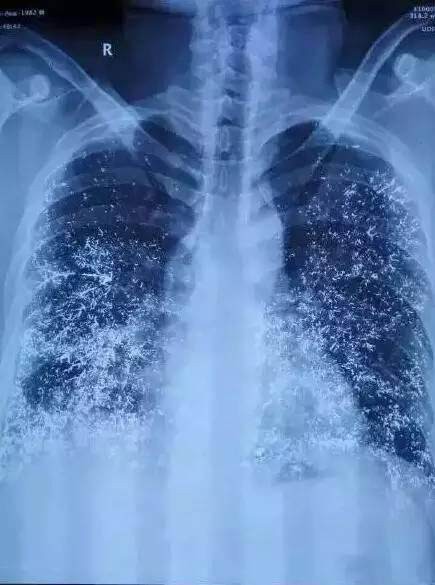

Nhiều cơ quan nội tạng của nạn nhân bị tổn thương nghiêm trọng.

Nạn nhân có thể phải mất cả đời để loại bỏ hết thủy ngân ra khỏi cơ thể.

Hành vi của Lưu Linh đã khiến bạn trai cô bị trúng độc nghiêm trọng, tổn thương tim, phổi, thận, đại tràng và tủy ở cấp độ 2, đến nay khả năng loại thải thủy ngân vẫn còn chậm. Với tình trạng này, nạn nhân Trần Hạo cần điều trị ít nhất 4 năm, thời gian trị bệnh có thể kéo dài 20 năm hoặc cả đời.